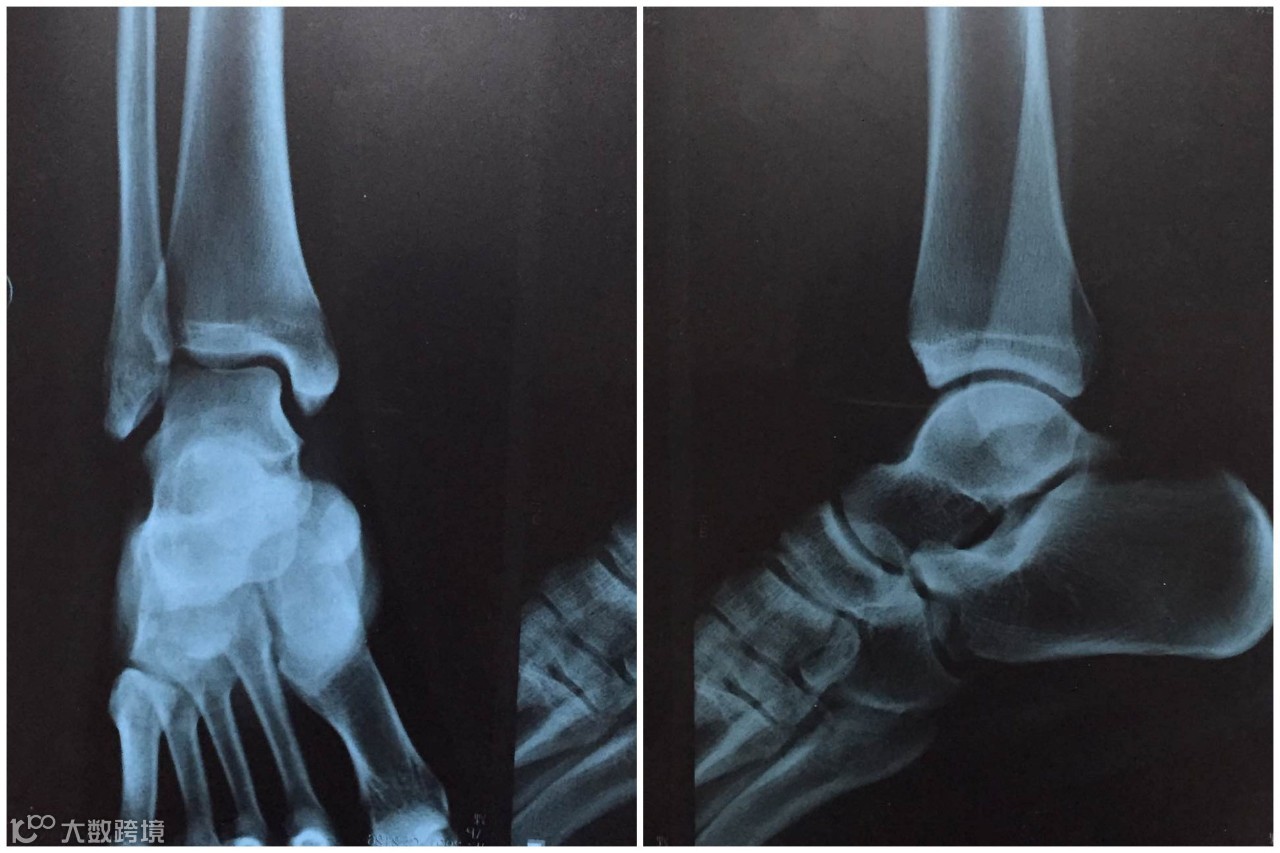

" 就在我俩在武汉站试音结束下台的时候,我从VOX后台的楼梯上意外摔了下来,咔咔两声崴伤了左脚,无比疼痛,幸好及时冰敷喷药。忍着剧痛表演完后,少华和他的朋友马上安排到了最近的医院拍片。好在骨头没事,轻微错位。现在我已经回忆不起当晚到底唱过什么说过什么了,只记得兄弟的搀扶和观众的敬意。谢谢华子,谢谢VOX的同仁,谢谢大家。”

X光片中可以清晰看出多出错位